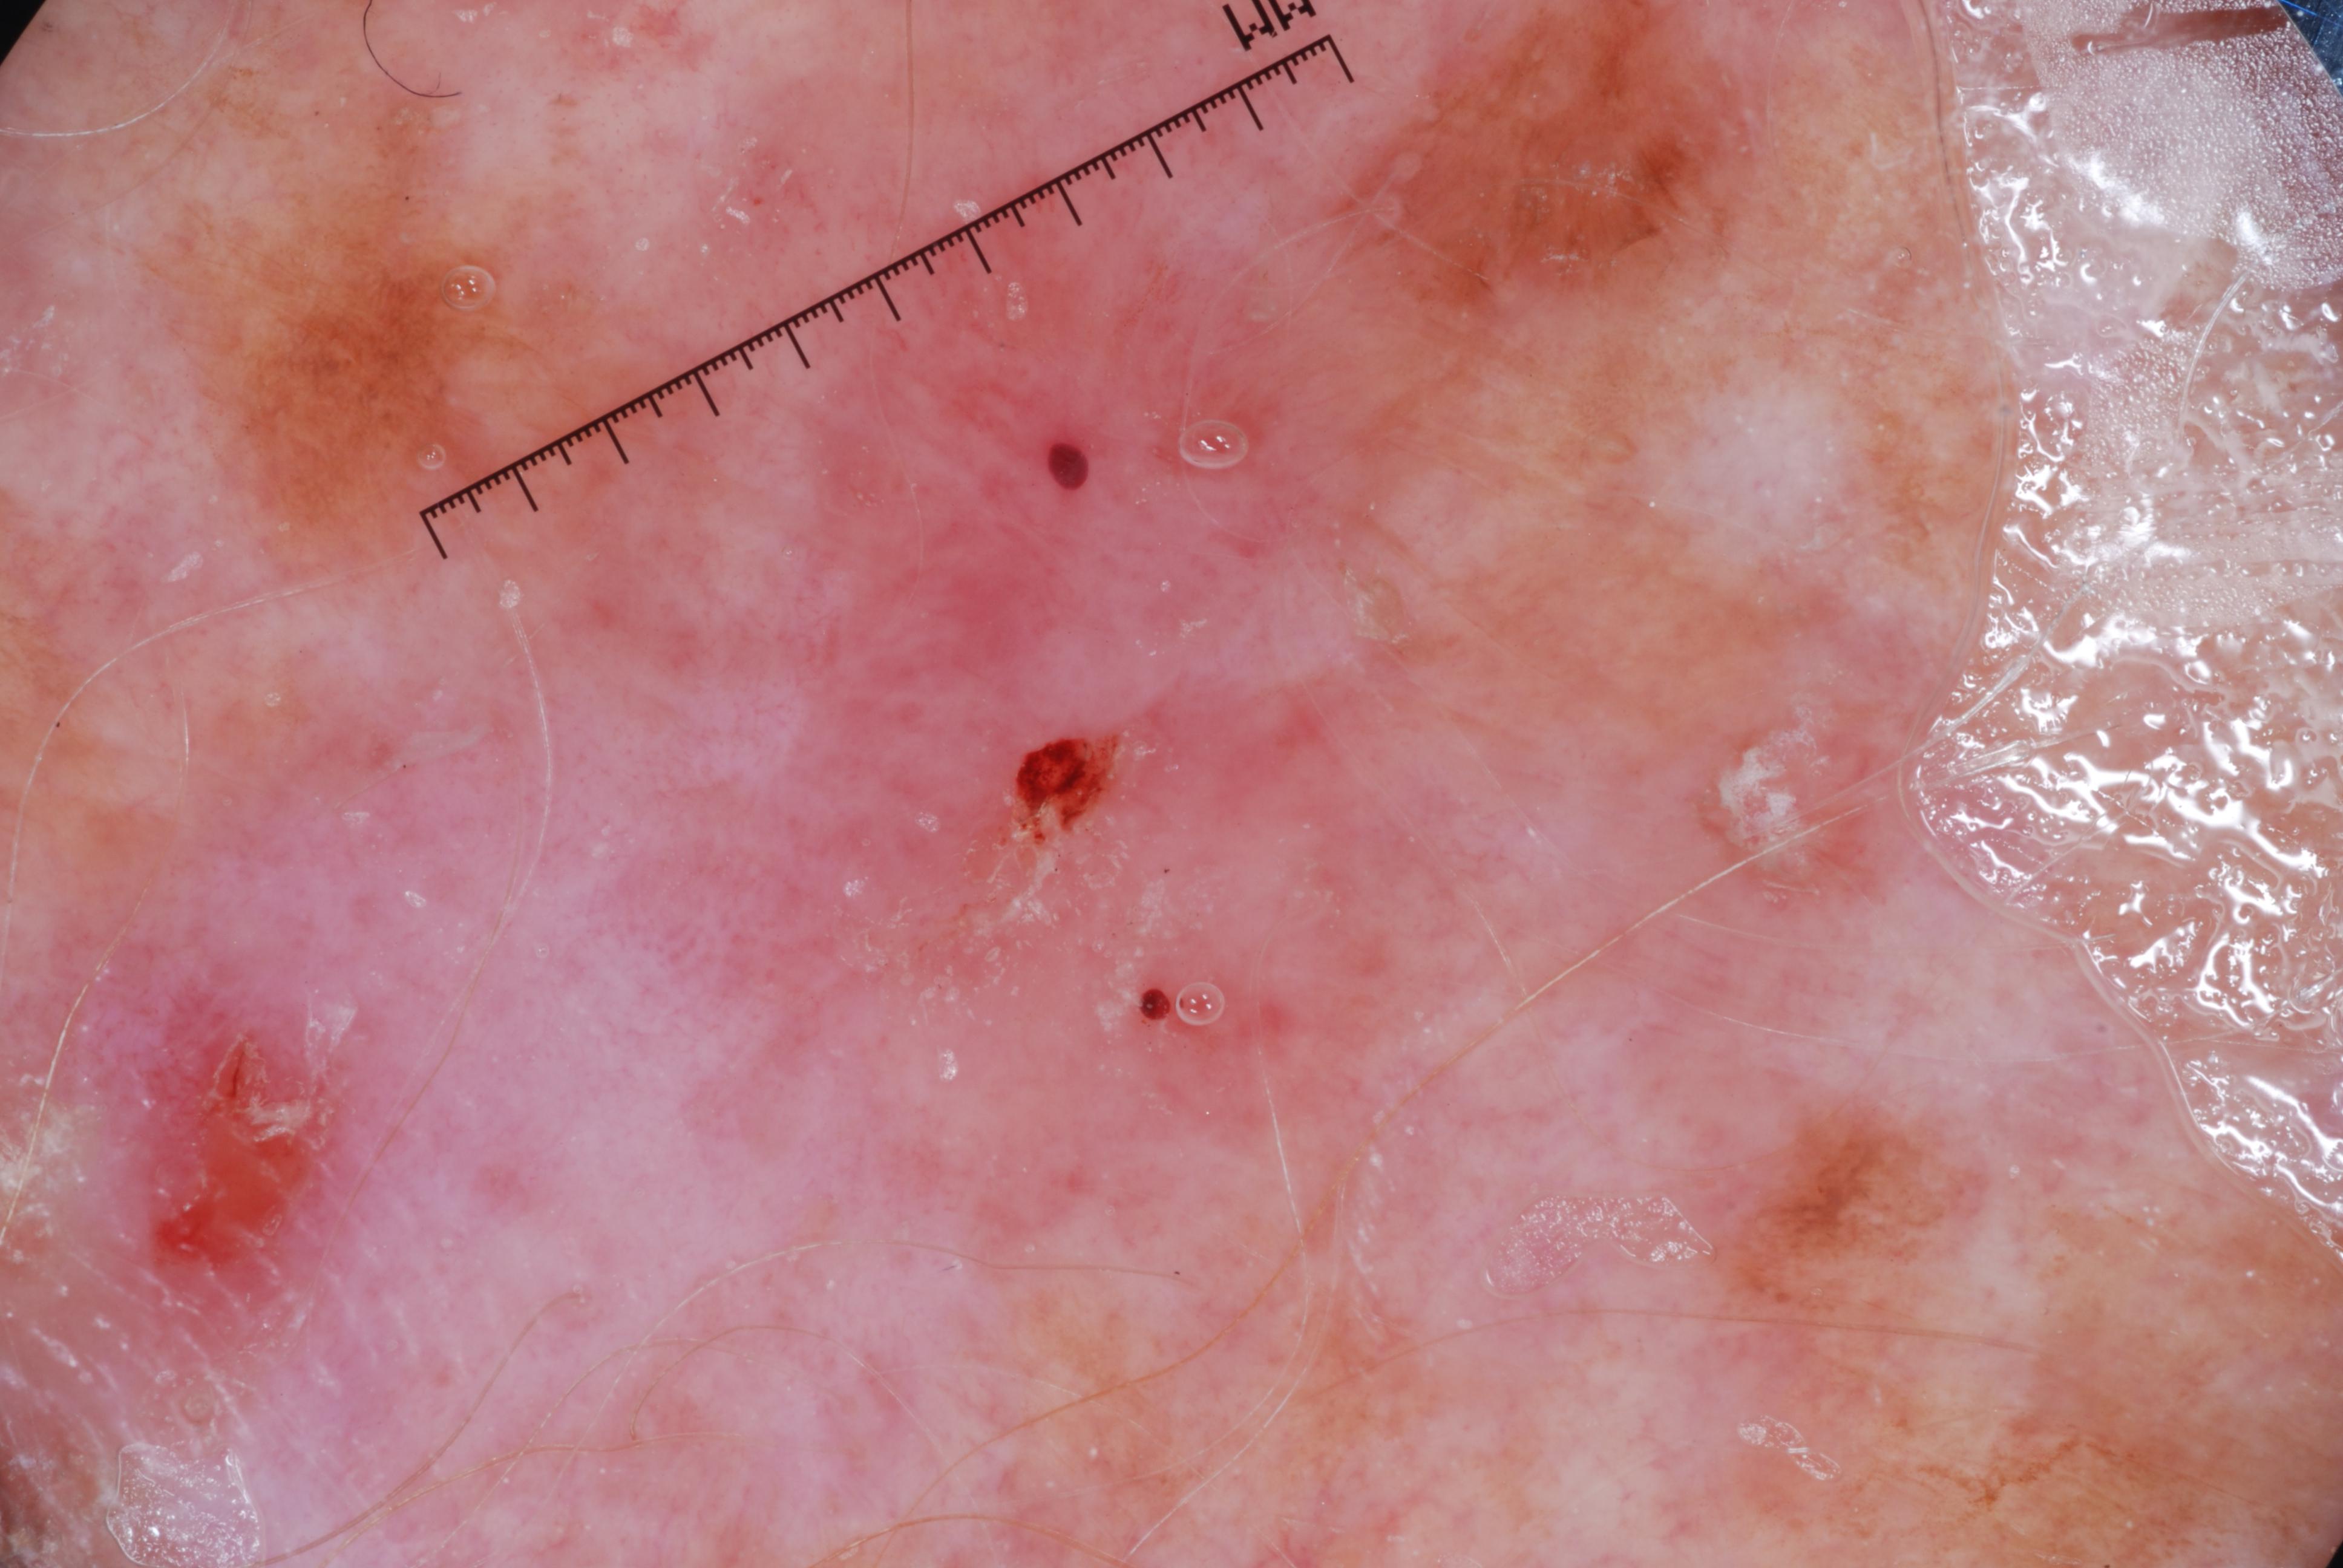

{

"age_approx": 70,

"anatom_site_general": "upper extremity",

"concomitant_biopsy": true,

"dermoscopic_type": "contact non-polarized",

"diagnosis_1": "Malignant",

"diagnosis_2": "Malignant epidermal proliferations",

"diagnosis_3": "Squamous cell carcinoma, NOS",

"diagnosis_confirm_type": "histopathology",

"image_type": "dermoscopic",

"lesion_id": "IL_8691737",

"melanocytic": false,

"sex": "male"